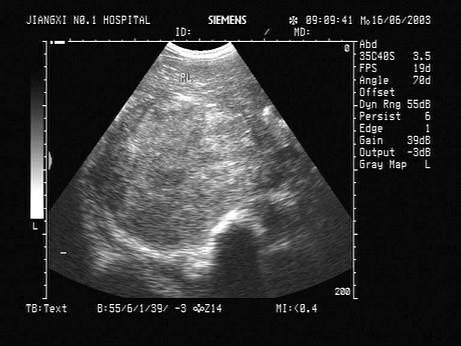

问题 男,50岁,右上腹疼痛,乏力,纳差。结合超声声像图,诊断为?(?)

选项 A.肝血吸虫病 B.巨块型肝癌 C.肝血管瘤 D.肝脓肿 E.肝囊肿

答案 B